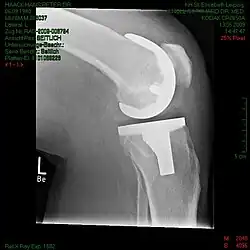

Ambulante Knie-Endoprothetik. Kasuistische Mitteilung.

Pat. H.-P.H., li. Knie 13.05.2009

Operation des linken Knie in Spinalanästhesie am 27. April 2009 mit Implantation einer bikondylären Endoprothese. Anschließend peridurale Infusion durch den Anästhesisten zur Ausschaltung des postoperativen Schmerzes. Nachts unerträgliche Steigerung des Restless-legs-Synroms unter der periduralen Infusion. Ratlosigkeit des Pflegepersonals. Die Bewegungsunruhe des Patienten wird als Unbotmäßigkeit empfunden, eine Entfernung der epiduralen Infusion abgelehnt. Der Dienstarzt operiert und kann nicht kommen. Statt dessen erhält der Patient eine zweite Schlaftablette. Er bittet daraufhin telefonisch seine Frau in die Klink. Sie soll zwei Gehstöcke mit Fritzgriff mitbringen, die sich im Haushalt des Patienten befinden. Der Pat. entfernt den Blasenkatheder, die venöse Infusion und kappt die peridurale Infusion. Die zwei Wunddrainagen samt angeschlossenen Flaschen belässt der Pat. Dem Dienstarzt, der nun doch erschienen ist, unterschreibt er ein Revers zur Entlastung des Krankenhauses. Mit den Stöcken, die Flaschen für das Wundsekret am kleinen Finger aufgehängt, geht er zur Nachtpforte des Krankenhauses, von wo ihn die Ehefrau auf der Rückbank des PKWs in die gemeinsame Wohnung fährt. Dort Entfernung des noch liegenden Spinaldrainage-Endstücks mit Beta-Isidona und Wunddesinfektions-Spray. Sistieren der Restless-legs-Symptome nach Abbruch der periduralen Infusion.